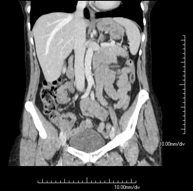

- TC Abdominopélvico

Prueba diagnóstica que consiste en obtener imágenes bi y tridimensionales del abdomen y de la pelvis de alta definición anatómica (estructuras óseas, estructuras vasculares, hígado, páncreas, vesícula biliar, riñones, glándulas suprarrenales, bazo, intestino delgado y grueso, vejiga, útero y ovarios, próstata y vesículas seminales, uréteres, etc.) mediante el empleo de un equipo de TC (Tomografía Computarizada). La mayoría de estudios requieren el empleo de contraste yodado.